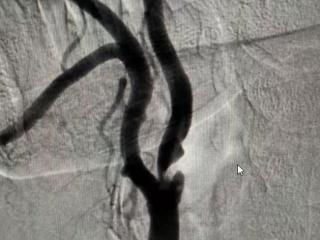

技术突破!青岛西海岸第二院脑血管病科成功开展山东省内首例 “应用IVUS指导下精准颈动脉狭窄介入治疗”